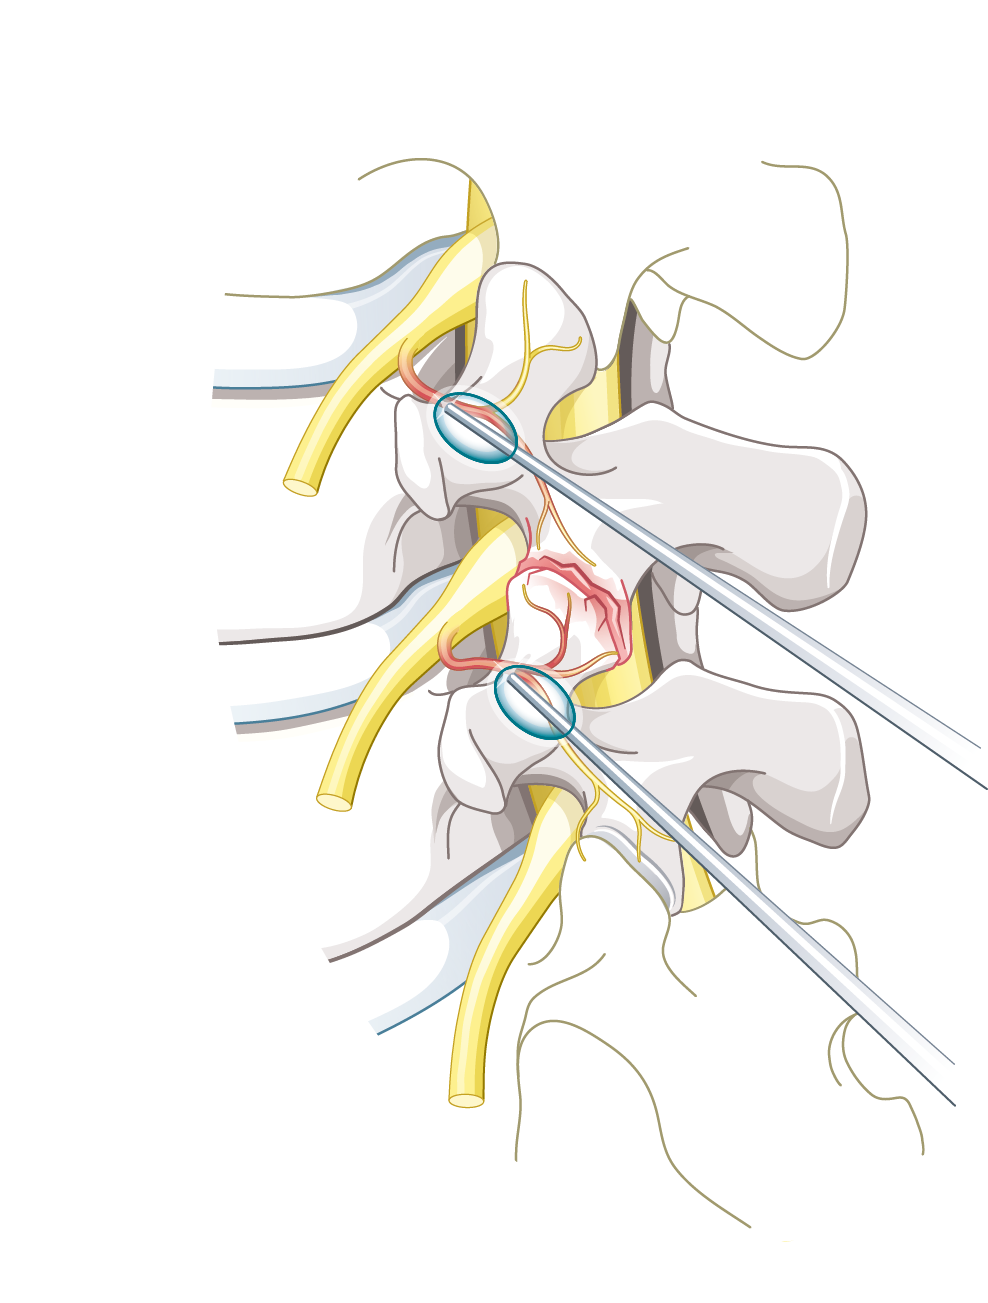

Therapeutische Infiltrationen dienen der zielgenauen Behandlung mit einem Medikament (oder Eigenblut). Infiltriert werden können je nach Leiden Gelenke, Bandscheiben, Nerven (diese, wie auch die Ganglien, werden bei der Infiltration nicht direkt getroffen sondern nur umspritzt), autonome Ganglien (Schaltzentralen des vegetativen Nervensystems), Muskeln, Faszienschichten etc.). Je nach Schmerzursache können Lokalanästhetika, Kortison, Hyaluronsäure, aber auch Botox oder Eigenblut verwendet werden.

Bei der Neuraltherapie wird ein Lokalanästhetikum direkt an den Nerv gespritzt. Obwohl Lokalanästhetika die Nerven jeweils nur für kurze Zeit betäuben, kann der Nerv häufig – nicht immer – mit diesem Verfahren in einen längerfristig schmerzärmeren- oder teils gar schmerzfreien Zustand geführt werden. Dieser Effekt kann verglichen werden mit einem Neustart des Computers; die kurze Betäubung des Nervs kann zu einem ‘Reboot’ oder ‘Neustart’ des Nervs führen. Dies gelingt vor allem dann, wenn einen neuroplastische Schmerkomponente vorliegt.

Teils ist es auch die Hydrodissektion – also das Auseinanderdrücken von Gewebeschichten durch Infiltration von Volumen – welche den therapeutischen Effekt erzielt. Dies kann beispielsweise bei Nerveneinengungen oder Faszienverklebungen der Fall sein.